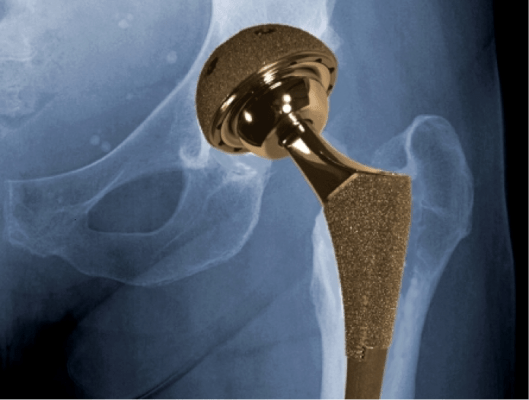

Metal-on-metal hip implants – either used as ‘cap’ for the femoral bone in a hip resurfacing procedure or as a full implant in total hip replacement surgery – are one of the more prevalent hip prosthetics, accounting for around 40,000 of all hip replacements.

All hip resurfacing procedures make use of metal-on-metal hip implants; however, most total hip replacements will utilise ceramic or highly durable polythene prosthetics. Generally, you’ll be made aware of which you are receiving pre-surgery.

When successful, it’s estimated that metal-on-metal prosthetics can offer pain-free mobility for around 10 to 15 years. However, concerns have been raised over the past few years as to the safety of ‘metal-on-metal’ hip implants. Although designed with durability in mind, some metal-on-metal implants can fail and the friction between the metal can lead to metal debris breaking off and entering the bloodstream.

The cobalt and chromium particles produced by the wear and tear of a metal-on-metal joint can concentrate around the hip, causing serious damage to tissue and leading to serious pain and discomfort for a patient.